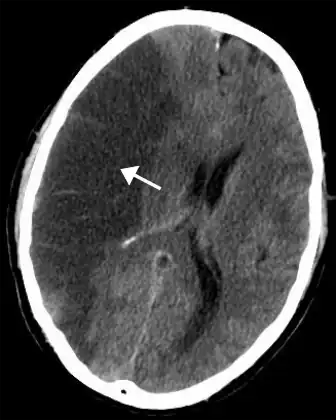

CT scan of the brain showing a prior right-sided ischemic stroke from blockage of an artery. Changes on a CT may not be visible early on.[1] | |

The biggest risk factor for stroke is high blood pressure.[7] Other risk factors include high blood cholesterol, tobacco smoking, obesity, diabetes mellitus, a previous TIA, end-stage kidney disease, and atrial fibrillation.[2][7][8] Ischemic stroke is typically caused by blockage of a blood vessel, though there are also less common causes.[13][14][15] Hemorrhagic stroke is caused by either bleeding directly into the brain or into the space between the brain's membranes.[13][16] Bleeding may occur due to a ruptured brain aneurysm.[13] Diagnosis is typically based on a physical exam and supported by medical imaging such as a CT scan or MRI scan.[9] A CT scan can rule out bleeding, but may not necessarily rule out ischemia, which early on typically does not show up on a CT scan.[10] Other tests such as an electrocardiogram (ECG) and blood tests are done to determine risk factors and rule out other possible causes.[9] Low blood sugar may cause similar symptoms.[9]

CT scans may not detect ischemic stroke, especially if it is small, of recent onset,[10] or in the brainstem or cerebellum areas (posterior circulation infarct). MRI is better at detecting a posterior circulation infarct with diffusion-weighted imaging.[71] A CT scan is used more to rule out certain stroke mimics and detect bleeding.[10] The presence of leptomeningeal collateral circulation in the brain is associated with better clinical outcomes after recanalization treatment.[72] Cerebrovascular reserve capacity is another factor that affects stroke outcome – it is the amount of increase in cerebral blood flow after a purposeful stimulation of blood flow by the physician, such as by giving inhaled carbon dioxide or intravenous acetazolamide. The increase in blood flow can be measured by PET scan or transcranial doppler sonography.[73] However, in people with obstruction of the internal carotid artery of one side, the presence of leptomeningeal collateral circulation is associated with reduced cerebral reserve capacity.[74]